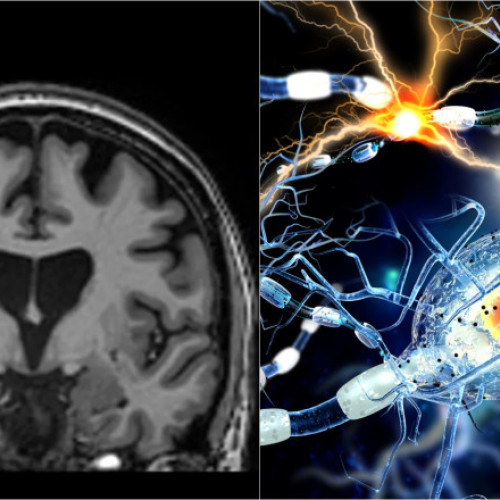

O premieră în tratarea bolii Huntington a fost realizată de compania de biotehnologie UniQure din Amsterdam. Studiul lor a arătat o reducere cu 75% a progresiei bolii la pacienții care au primit un tratament genetic inovator, ce utilizează o tehnică bazată pe micro-ARN.